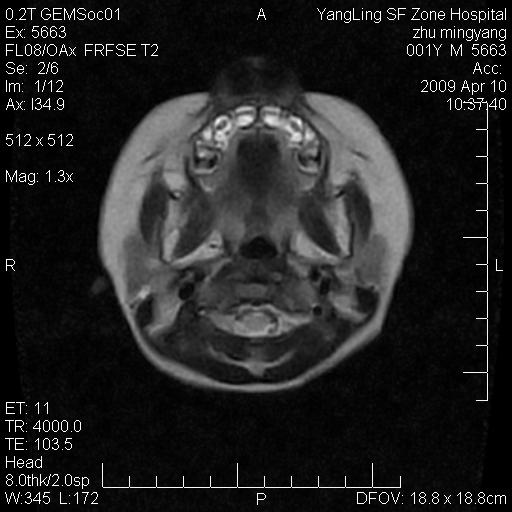

患者:1岁半,两天前外伤收住我院,ct检查小脑占位

考虑星形细胞瘤,建议增强

髓母细胞瘤或血管母细胞瘤,增强后可以鉴别;影像资料见 <。鱼博浪老师的《中枢神经系统ct与mr鉴别诊断》 小脑部肿瘤章节。

髓母细胞瘤或血管母细胞瘤!支持!

支持考虑髓母细胞瘤

考虑----髓母细胞瘤可能性大

考虑髓母细胞瘤或室管膜瘤。

支持髓母细胞瘤。

考虑髓母细胞瘤。

考虑髓母细胞瘤或星形细胞瘤

考虑髓母细胞瘤.

考虑髓母细胞瘤可能性大。

小脑肿瘤.考虑髓母细胞瘤可能.

就病灶部位及临床资料首先考虑髓母.